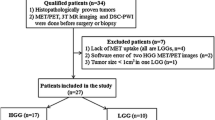

Twenty-four patients (>18 year) presenting with suspected LGG referred to the Neurosurgery Department, Uppsala University Hospital, between February 2010 and September 2012 were enrolled and investigated by morphological MRI, pMRI and dMRI according to the study protocol. The institutional review board approved the study and written informed consent was obtained prior to participation. Inclusion criteria were clinical and morphological MRI findings suggestive of LGG, and a maximum time interval between PET and MRI of 90 days. Radiological diagnosis was based on typical appearance on morphological MRI with T1-weighted MRI showing no or minimal contrast enhancement. Clinical exclusion criteria were the presence of major neurological or cognitive deficits suggestive of HGG. MET PET findings were incorporated in clinical decisions to obtain early histology-proven diagnosis but high MET uptake suggestive of HGG did not exclude patients from the study [14].

Twenty-four patients (12 males, 12 females) with mean age of 48.9 years (SD ± 15.2, range 22–78 years) at radiological diagnosis were included. Twenty-two patients (92 %) presented with epileptic seizures and received antiepileptic drugs, two patients with minor neurological symptoms such as dizziness and headache. Clinical, histological and radiological tumor characteristics are summarized in Table 1.

Histological diagnosis

Tumor diagnosis was confirmed in 23 patients (Table 1). Tumor diagnoses consisted of glioma grade II (n = 18; 8 astrocytomas grade II; 6 oligodendrogliomas grade II; 3 oligoastrocytomas grade II; 1 ganglioglioma grade II) and glioma grade III (n = 5; 3 astrocytomas grade III; 1 oligodendroglioma grade III; 1 oligoastrocytomas grade III) (Table 1). Microsatellite analysis confirmed the presence of LOH 1p/19q in 9/11 tumors (82 %) with an oligodendroglial component. Patient 5 had biopsies from six different locations in the tumor-suspected area without histological proof of tumor and was diagnosed with non-specified encephalitis.